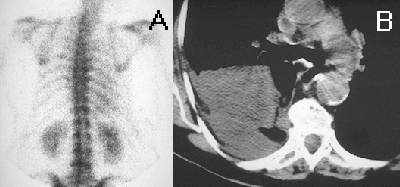

SeminomaSeminoma

(A) The bone scintigram in anterior projection demonstrates abnormally increased radionuclide activity in the mediastinum. There is a bulky soft tissue mass occupying the mediastinum on this axial CT (B) of the chest, that displaces the thoracic aorta posteriorly. The mediatinal mass is biopsy-proven seminoma.